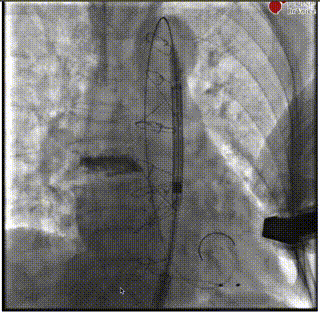

释放前造影确定位置和深度

完全释放

最后造影

术后超声

闭合血管入路,完成手术。本例难点在于SAVR术后结构性瓣膜衰败导致主动脉瓣反流,原外科瓣膜未见钙化,术前经充分沟通,确定植入深度于瓣架第一节点与第二节点间,保证瓣架底部在外科瓣膜环上具有足够锚定力。术中,瓣架完全释放前小弯侧深度稍大于大弯侧,微量PVL,在最终时提示术者对递送系统轻微施加推力,释放后两侧深度达到平衡,PVL消失,平均压差2mmHg,舒张压即刻恢复正常。